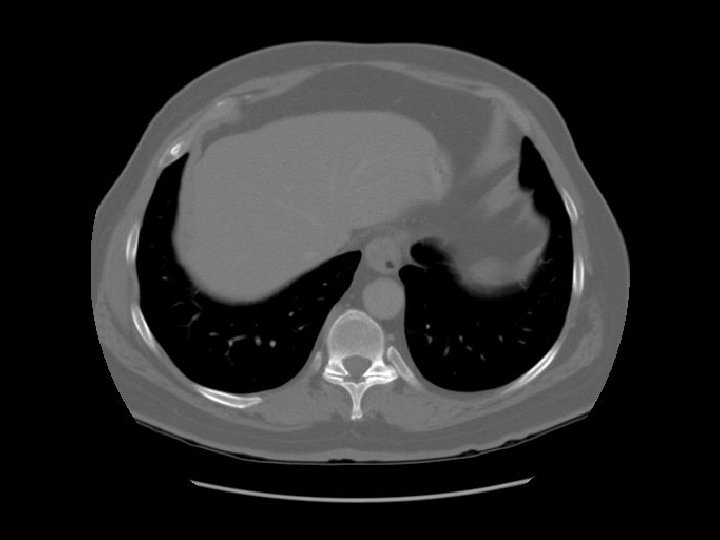

Liver Heart

Stomach GE junction Esophagus

Stomach Liver Spleen

Lt lobe Rt lobe